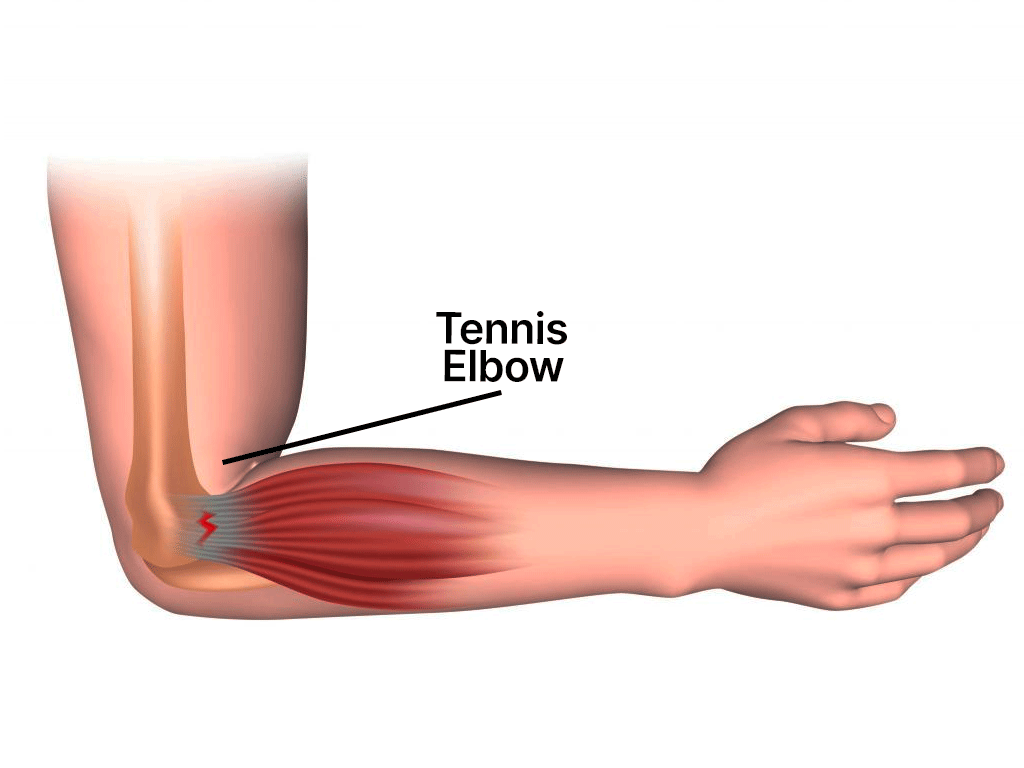

Elbow

Chronic sports injuries develop over time due to overuse or repetitive stress. Common examples include tendinitis, shin splints, and stress fractures. Here’s how to manage them:

Tendinitis